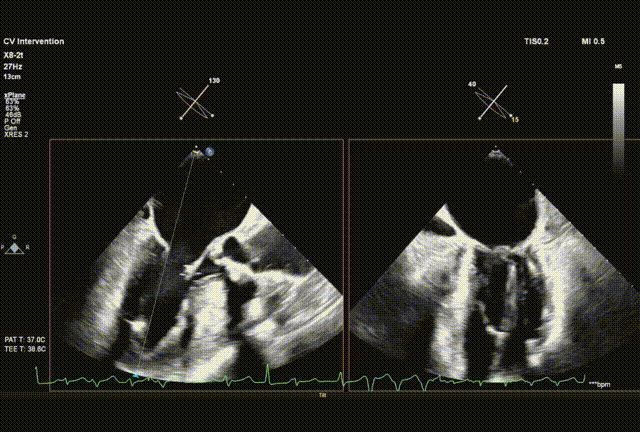

球囊预扩

输送系统顺利跨瓣

瓣膜初始释放到喇叭状形态并定位植入深度

采样线扫到无窦,180起搏,长轴视图下快速释放到工作位

超声从左至右,最后无冠窦侧评估深度合适